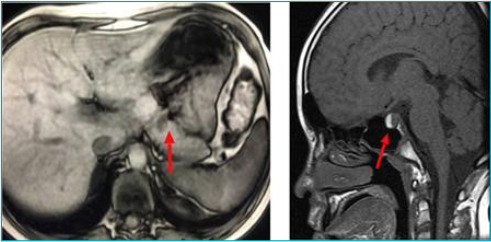

Case description: An 11-year-old boy began to present generalized tonic-clonic seizures in the presence of hypoglycemia, with high insulin dosage, leading to suspicion of insulinoma. Abdominal magnetic resonance imaging confirmed a pancreatic nodule, which was surgically resected, resulting in glycemic normalization. Low growth hormone levels and hyperprolactinemia, secondary to macroprolactinoma, were also identified. Treatment with cabergoline led to a reduction in size. Hyperparathyroidism was found asymptomatically, with parathyroid scintigraphy suggestive of adenoma, thus, the patient underwent subtotal parathyroidectomy and thymectomy with resolution of the condition. He entered puberty spontaneously at 15 years of age; however, he had decreased growth speed, short stature, and low insulin-like growth factor 1 (IGF-1) levels, indicating recombinant growth hormone. The next-generation sequencing panel for multiple endocrine neoplasia type 1 identified a probably pathogenic variant c.442A>C: p.(Thr148Pro) in heterozygosity in the MEN1 gene, without previous description in databases (ClinVar).

Comments: We highlight the pre-pubertal age of multiple endocrine neoplasia type 1 diagnosis, which is made before age 21 in only 12-17% of cases, and hypoglycemia secondary to insulinoma as the initial manifestation, differing from what is most frequently described, namely prolactinoma and parathyroid adenoma. The clinical diagnosis was made based on the occurrence of two primary endocrine tumors and confirmed through a next-generation sequencing panel, with a variant not previously described in ClinVar.